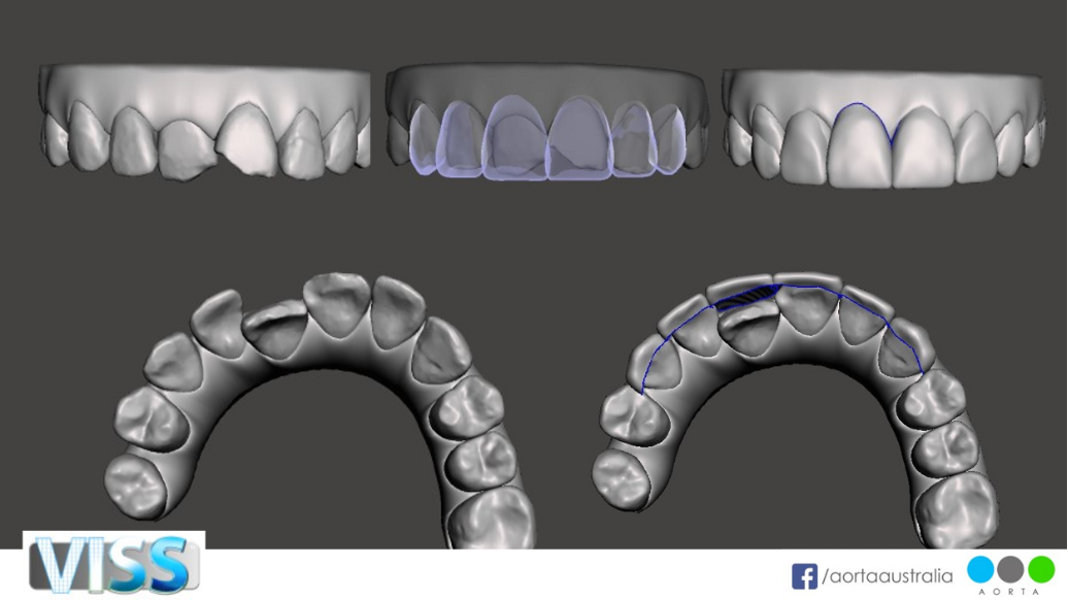

In this third section, we will explore how clear aligner simulations with Virtual Interdisciplinary Smile Simulation (VISS) can be digitally enhanced to demonstrate restorative augmentation after orthodontic treatment. This digital diagnostic and treatment planning service from AORTA digital laboratory has evolved since 2018 and is able to create a digital simulation of treatment with any aligner system, as well as of any direct or indirect restorative treatment or soft-tissue augmentation.

This concept of a virtual smile simulator evolved from the notion of seeking to create patients’ emotional connection to treatment through the clear aligner software. Its purpose is better smile creation by digitising the diagnosis, treatment planning and patient engagement process. This software enables the clinician to better diagnose and plan treatment using aesthetic orthodontic, prosthodontic and facial aesthetic principles from an extra-oral, perioral and dentition perspective.

When evaluating the STL files after clear aligner simulation of any aligner system, the clinician can assess whether there are hard- or soft-tissue augmentation options. From the soft-tissue perspective, if there is asymmetry of the zenith heights of the anterior gingival tissue or a need to lengthen tooth dimensions, this can be digitally simulated. The tooth perspective of the post treatment STL file can digitally simulate direct or indirect restorations to optimise the golden proportions regarding tooth length–width ratio. This can provide choices for both the clinician and the patient. This digital workflow can also provide superior informed choice pre- and post-treatment with clear aligners by simulating a restorative-only solution for comparison with the clear aligner simulation.

Figs. 34a–e: Simulated VISS images showing the situation pre-treatment (a & d), post-treatment (c & e) and after restorative treatment (purple).

Figs. 36a–e: Simulated VISS images showing the situation pre-treatment (a), post-treatment (b & e) and after restorative treatment (purple; c & d).